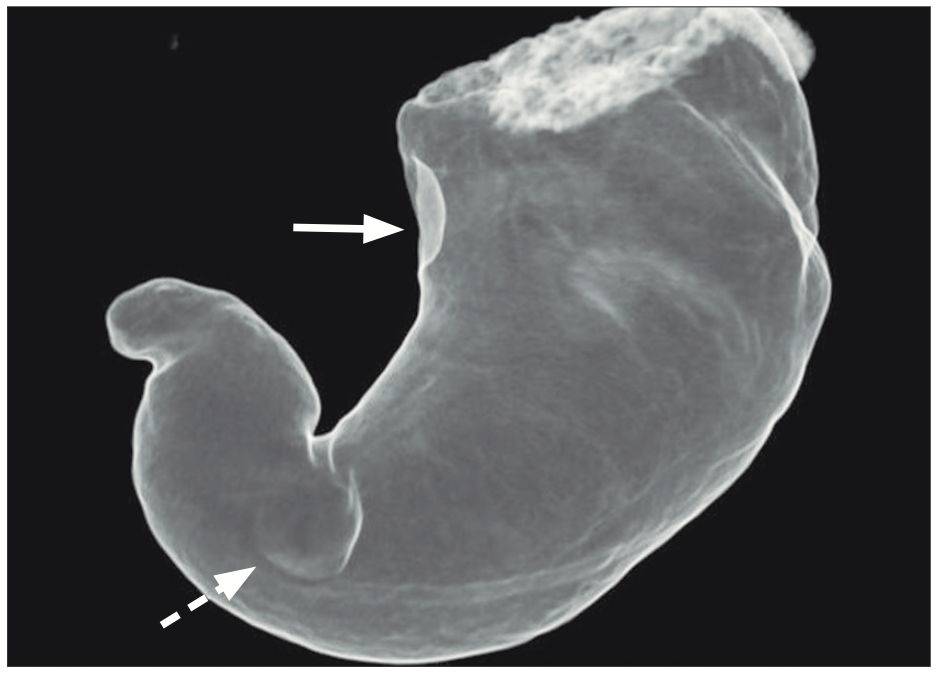

La tomografía computada prequirúrgica evidenció una masa subcardial con crecimiento hacia la luz y realce homogéneo tras la administración de contraste, y otra masa en el cuerpo distal de crecimiento mixto y realce heterogéneo (Figuras 1A y 1B). La reconstrucción tridimensional, similar a un estudio baritado del estómago, facilitó la localización precisa de ambos tumores (Figura 2). La endoscopía virtual proporcionó una visión intraluminal de ambas lesiones; mostrando la mucosa gástrica preservada (Figura 3). No se evidenciaron adenopatías regionales ni metástasis a distancia.

Figura 2.